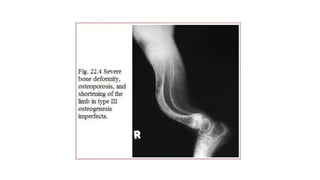

This document discusses a disease and its investigation and management. It begins by introducing Dr. Aniket Wankhede from MGIMS Sevagram and asks what the disease is. It then asks how the disease happens and discusses its causes. Next it asks how the disease appears on x-rays and describes symptoms some people experience living with it. Finally, it asks how the disease will be investigated and managed.